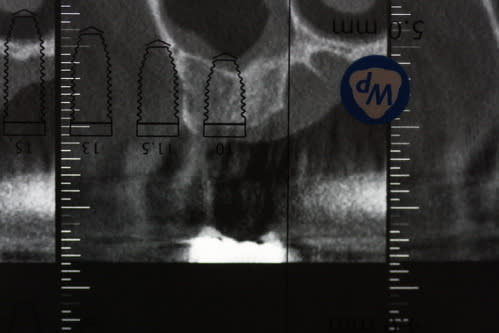

cas tout frais de cette après-midi

passage uniquement des ostéotomes pour cette 17 extraite il y a 3 mois 1/2

ostéotome à 6 mm:

1,5 à 2,2

2,2

2,8

3,5

bio-oss avec le 3,5

un coup de 4,2 sur 2 mm pour marquer l'entrée

mise en place d'un WP speedy: stabilité final de 30 N

mise en place de la vis de cica

1 point blair donati modifié et hop 40 mn